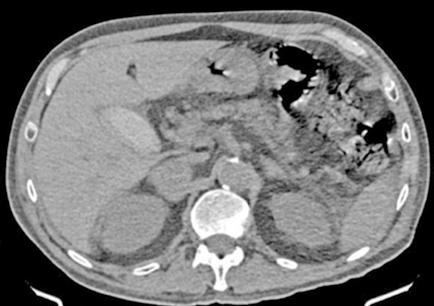

Figura 1 (A, B y C).

Imágenes de TC: Gran masa hepática localizada en segmentos VII, V y parte del IV. Signos de sangrado no activo.

A)Masa localizada entre VSH media y derecha.

B) Masa en contacto con rama portal.

C) Imagen en 3D donde se ve la gran masa y su relación con el resto del hígado.